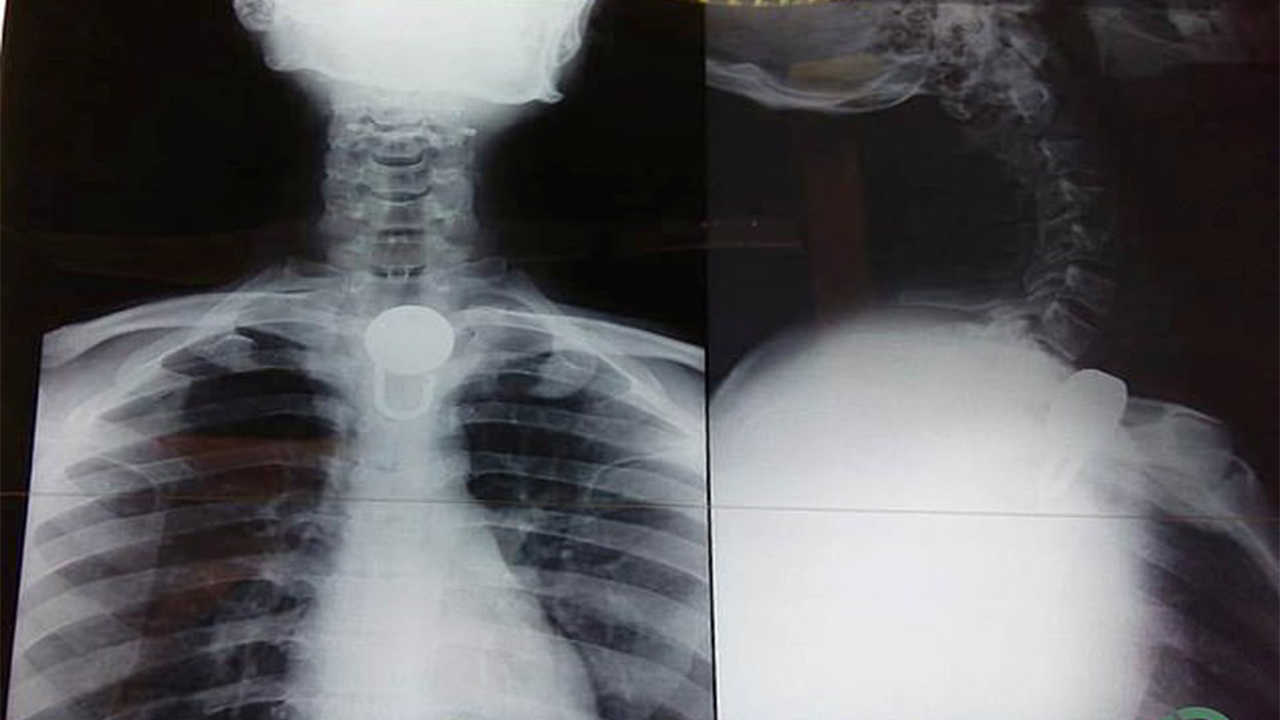

أخرج أطباء في الهند قفلاً علق في حلق شاب، 22 عاماً، قام أهله بتقييده بالسلاسل منعاً لهروبه، فقام بابتلاع القفل، وفقاً لما جاء في موقع "ديلي ميل" البريطاني.

وابتلع الشاب الذي يعاني مشكلات في الصحة العقلية، القفل الذي يبلغ طوله ستة سنتيمترات بعيداً عن أعين عائلته.

ولم يتمكن الأطباء من إزالة القفل بالتنظير غير الجراحي، لذلك اضطروا إلى إجراء عملية جراحية مدتها أربع ساعات لإخراجه.